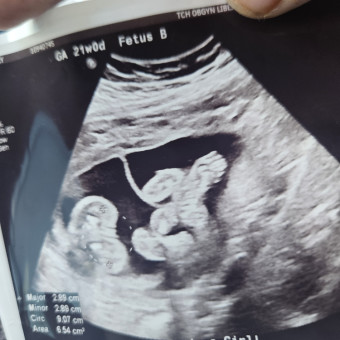

We are so excited (and a little nervous!) as we get ready to welcome our two sweet babies this winter. Our due date is January 10th but it's looking like they will be here sometime before Christmas! With twins arriving in the coldest months, and this being our first NORTHERN Winter experience with newborns, we’re focusing a lot on cozy, practical, and double-the-love essentials to help us stay prepared.